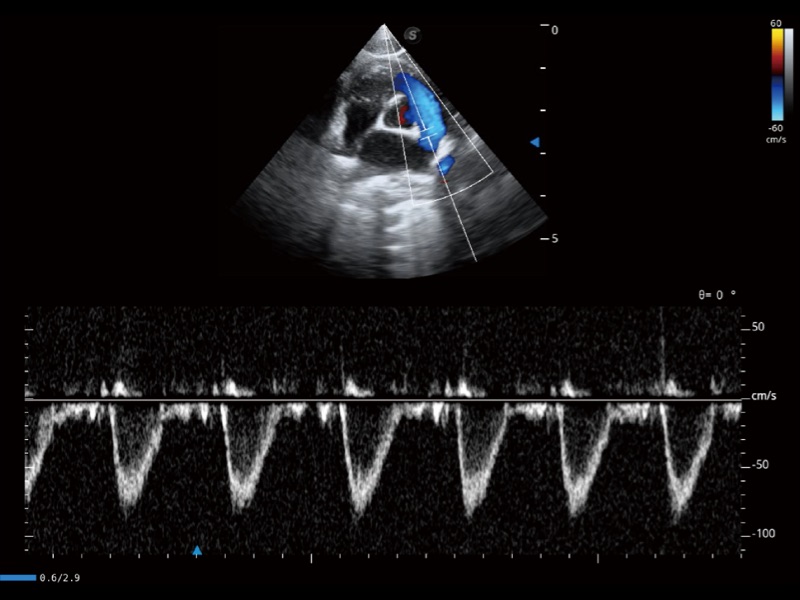

优异的基础图像

ProPet 70 全新的动物超声智能软件和丰富的探头群,为动物医生提供了高清晰度和精细分辨率的图像,无论在宠物、马科、畜牧还是实验室动物等应用中都可以轻松应对,为您的日常工作带来满意的体验。

(猫)肺动脉血流频谱